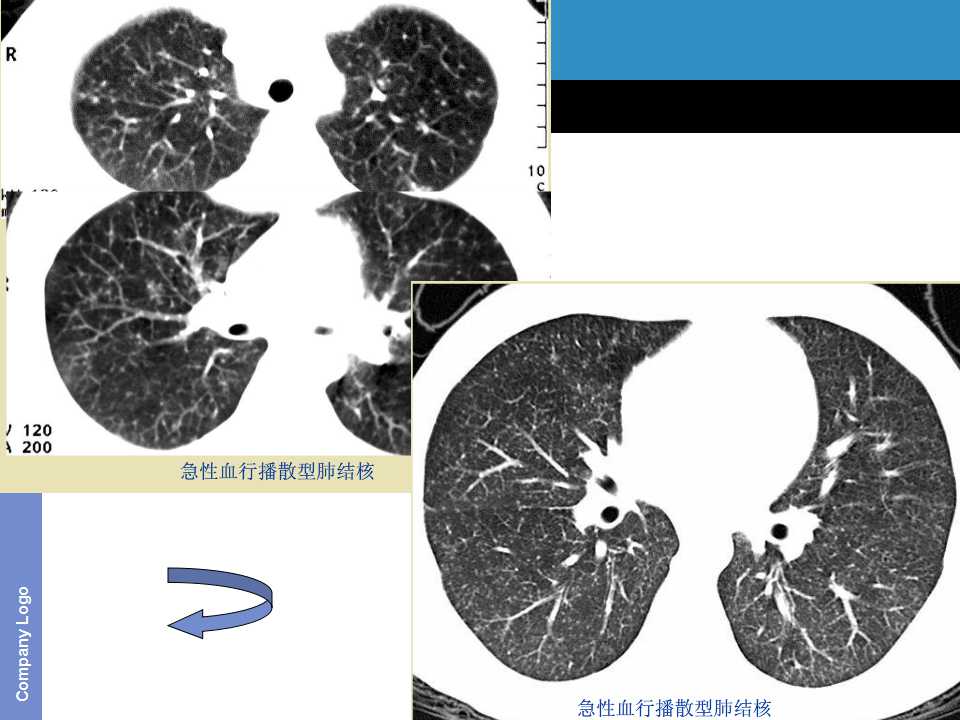

肺癌影像诊断